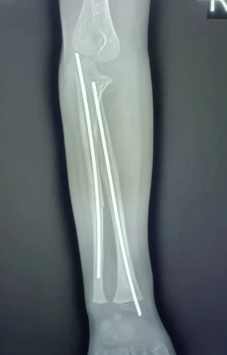

入院后我科于2023年08月17日下午在全身麻醉下行右侧尺挠骨骨折封闭复位+髓内针内固定术,术后第二天如下图示:

术后给予抗炎、消肿、止痛及中医康复训练等综合治疗后,患儿术口愈合良好,肢体功能恢复良好,肌力、肌张力正常。